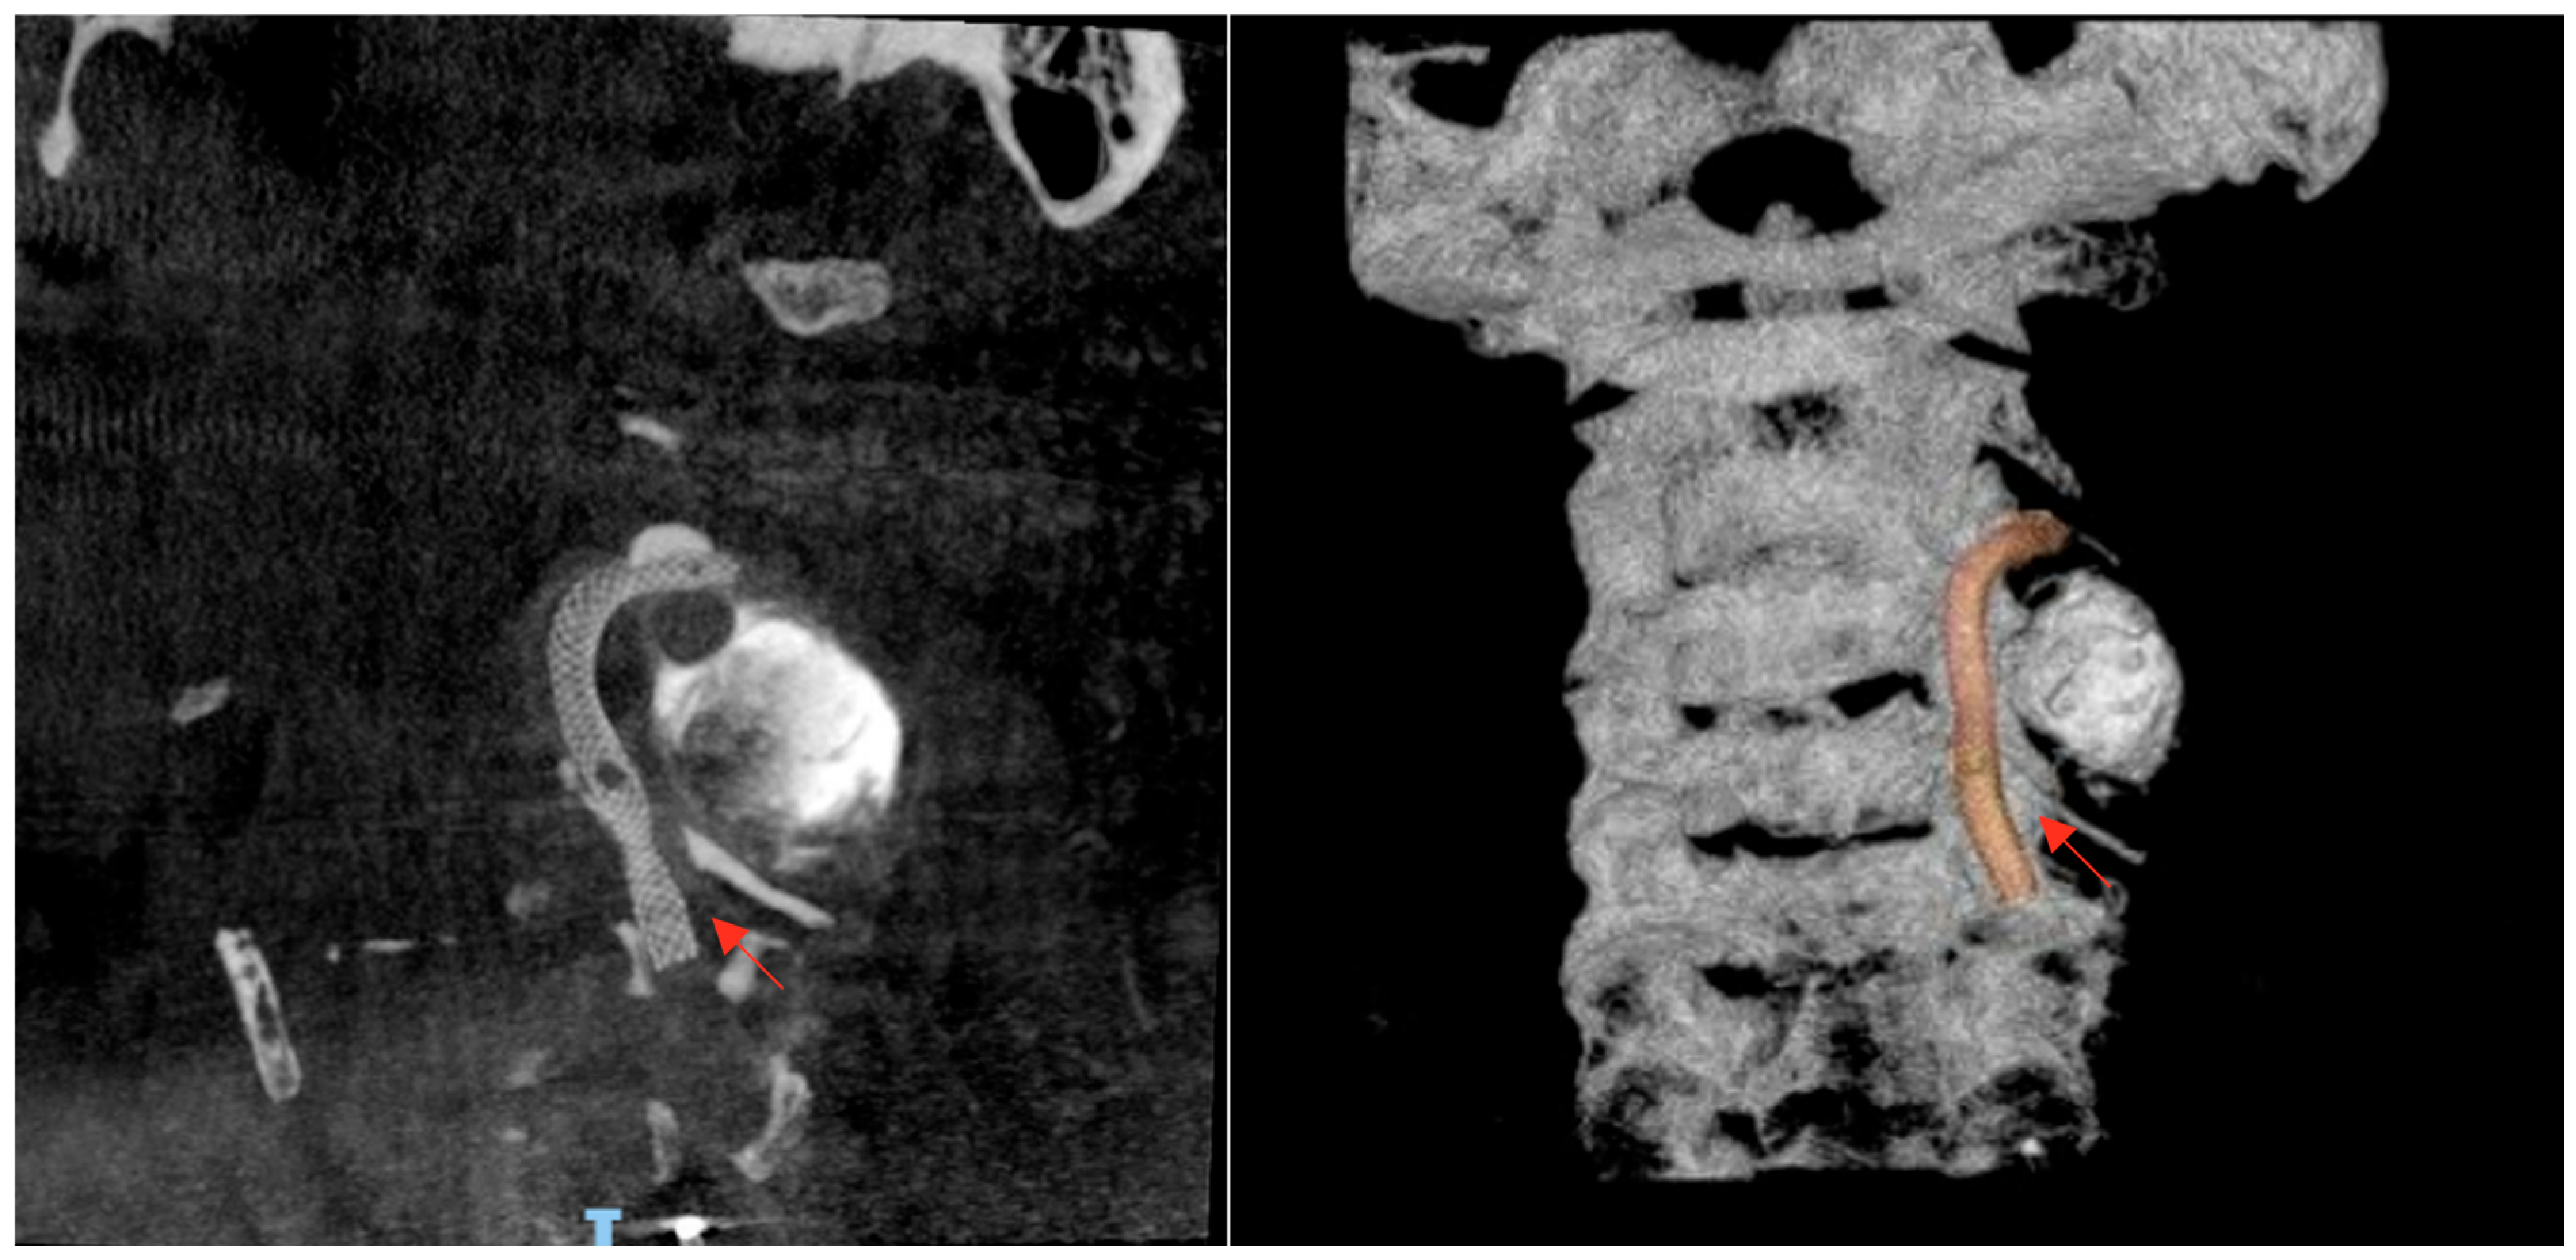

Neuroimaging was performed immediately. Non-contrast head CT revealed hypoattenuation in the parasagittal left occipital lobe, consistent with acute infarction. MRI of the brain confirmed acute ischemic lesions, showing multiple focal hyperintense lesions on T2/FLAIR with restricted diffusion involving the left occipital lobe, the left cerebellar peduncle, and both cerebellar hemispheres, more extensive on the right side, consistent with an embolic pattern of infarction (Figure 1).

Figure 1. Brain magnetic resonance imaging (MRI): (AC) Axial diffusion-weighted imaging (DWI) sequence (TR/TE = 3600/90 ms), showing multiple focal lesions in the left occipital lobe, left cerebellar peduncle, and both cerebellar hemispheres, more prominent on the right side. These lesions demonstrate marked diffusion restriction, consistent with acute embolic infarction. (D,E) Axial T2-weighted FLAIR sequence (TR/TE = 9000/120 ms), showing corresponding hyperintense signal abnormalities. (F) Axial gradient-echo T2* sequence (TR/TE = 700/20 ms), demonstrating no evidence of intracranial hemorrhage. Source: patient’s medical record, with prior authorization.